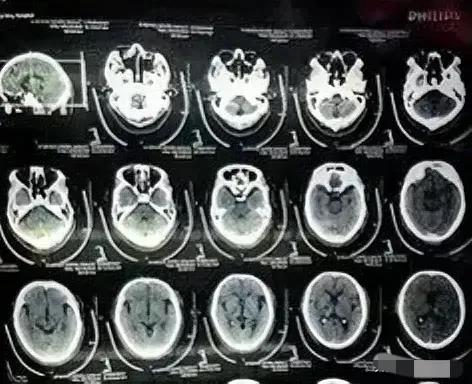

出院后的20多天,朱大伯病情还算稳定,但是到了5月4号这天,朱大伯又突发病情,被家人紧急送到了县人民医院,随后医生要求患者拍了ct,发现颅内段部分动脉已严重堵闭,同时,并未发现植有支架,随后家人赶到市医院复查,最终还是没有发现支架,突然家人们都不淡定了